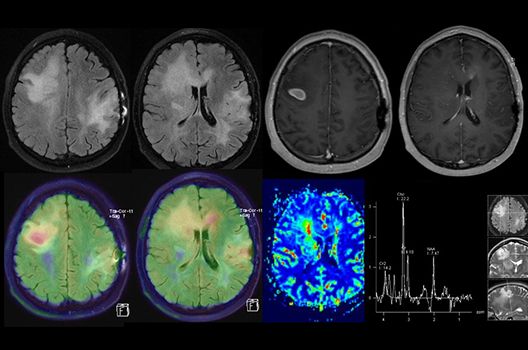

Die Schwerpunkte in der MR-Forschung liegen in der multiparametrischen und funktionellen Bildgebung bei onkologischen und anderen, neuroradiologischen Fragestellungen und umfassen die Anwendung modernster MR-Verfahren sowie die Untersuchung an Hochfeld-Geräten.

Die Magnetresonanztomographie (MRT) ist ein Verfahren, bei dem durch magnetische Kräfte Bilder des Körperinneren angefertigt werden. In der Neuroradiologie können manchmal kleinste Veränderungen schwere Folgen haben; daher forschen wir an der Entwicklung hochauflösender MRT-Sequenzen, mit denen diese Prozesse und auch einzelne Nervenfaserbahnen sichtbar gemacht werden können. Darüber hinaus sind bei vielen Erkrankungen des Gehirns die Blutgefäße betroffen. Daher arbeiten wir an der Neu- und Weiterentwicklung von MRT-Sequenzen zur Darstellung der Blutgefäße und zur Blutflussanalyse (sog. „Angio-MRT“). Einen besonderen Forschungsschwerpunkt unserer Klinik stellen die MR-Protonenspektroskopie und die funktionelle MRT dar, mit denen die Analyse einzelner chemischer Substanzen im Hirngewebe oder die Darstellung ausgewählter Hirnfunktionen möglich ist.

Die Hybridbildgebung mittels PET/MRT spielt insbesondere in der onkologischen Bildgebung eine wichtige Rolle. Eine mögliche Fragestellung ist die Unterscheidung zwischen einem Tumorrezidiv oder therapeutisch assoziierten Veränderungen insbesondere dann, wenn diese Frage mittels MRT alleine nicht beantwortet werden kann.

Die bildgebende Diagnostik und Verlaufsbeurteilung von Tumoren des Nervensystems ist einer der klinischen und Forschungsschwerpunkte unserer Abteilung. Eine besondere Bedeutung kommt der Hybrid-Bildgebung zu. Das Universitätsklinikum verfügt über einen integrierten Ganzkörper-PET/MRT-Scanner, der die Vorteile der MRT-Bildgebung und der Positronenemissionstherapie (PET) vereinigt. Aufgrund der langjährigen klinischen Arbeit und Forschungstätigkeit mit diesem Gerät hat die Neuroradiologie Tübingen maßgeblich zur Etablierung dieses Verfahrens beigetragen. Auch weiterhin forschen wir intensiv an neuen Methoden zur frühen Einordnung von Tumoren und insbesondere Tumorrezidiven, die mit anderen Methoden häufig nicht erfasst werden können.